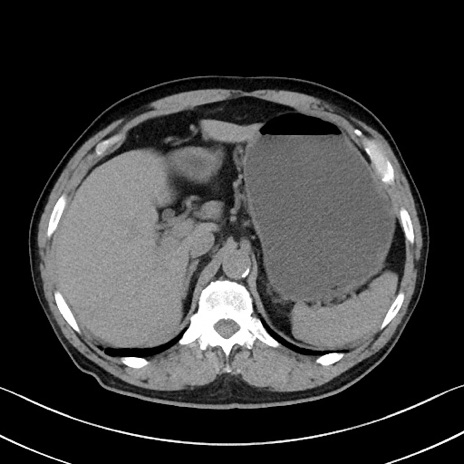

症例35(横断像)

【症例】70歳代 男性

【主訴】腹部膨満、嘔吐

【現病歴】昨日より腹部膨満感出現。本日増悪し、仙痛出現。嘔吐あり、受診。

【既往歴】糖尿病、胆摘後

【身体所見】BP 149/80mmHg、HR 74/min、BT 35.9℃、腹部:膨満、軟、圧痛なし。腸雑音減弱あり。上腹部正中切開瘢痕あり。

【データ】WBC 13500、CRP 1.72